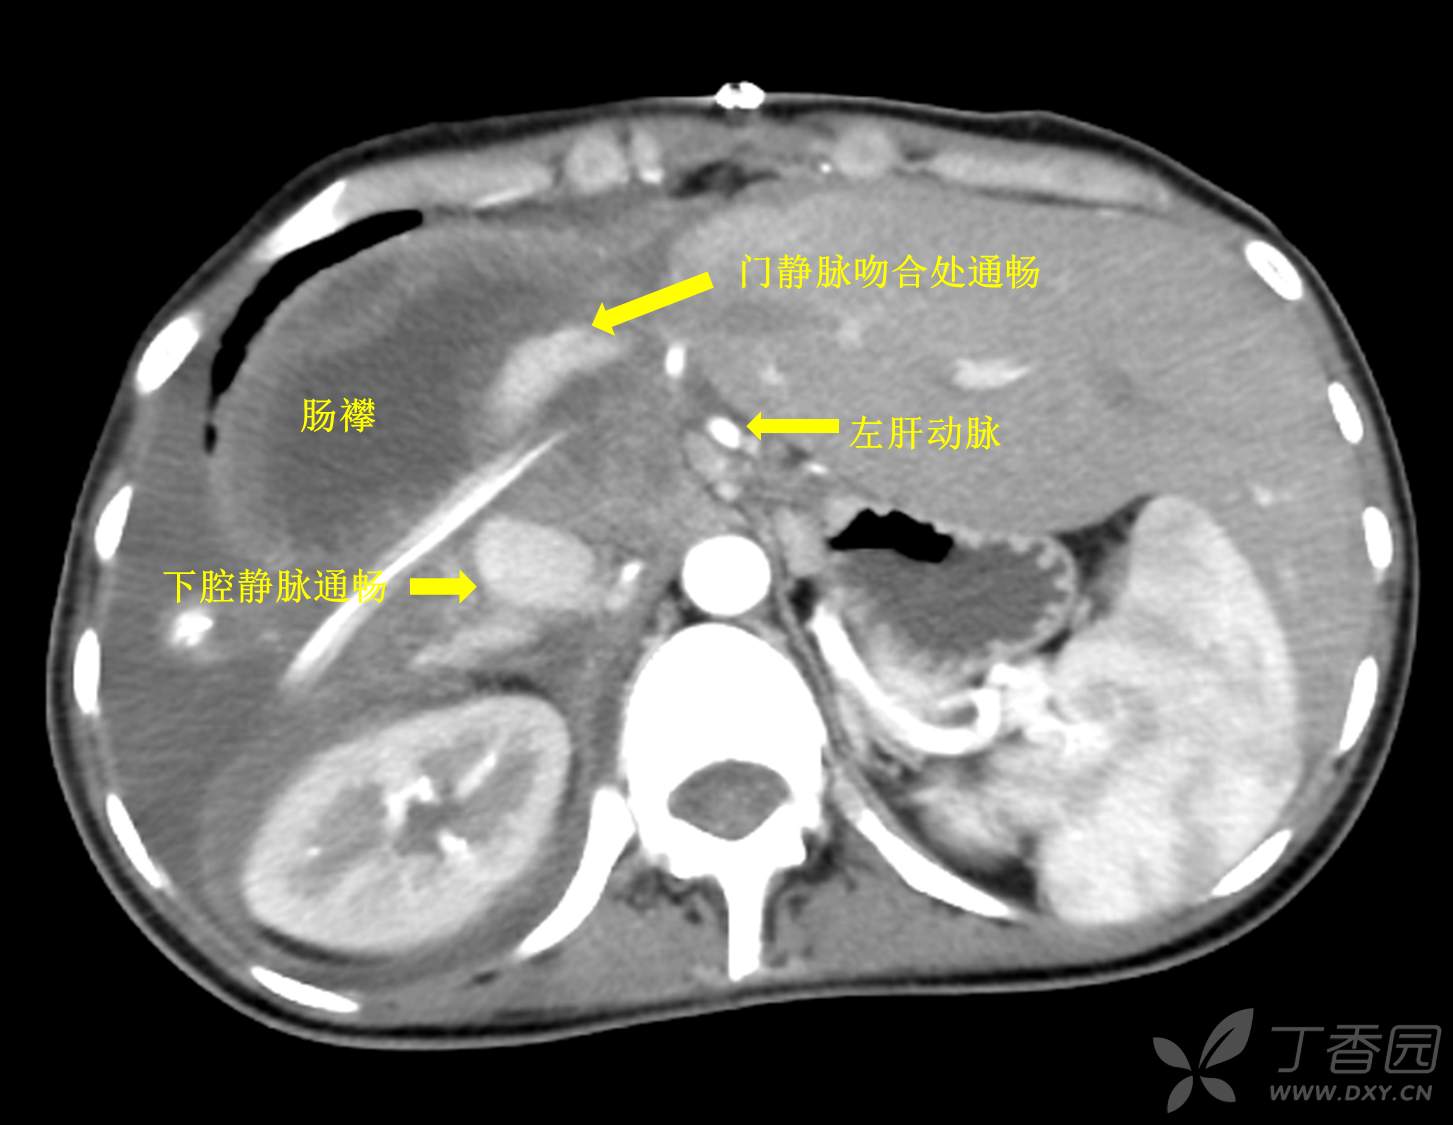

术后恢复顺利,顺利拔管出院。拔管前影像资料如下:

(me:我问主刀,那个下腔静脉部分切除后会不会窄。答曰,这个不窄。术后从病人恢复情况看确实不窄。各位看官,如何判断修补后的下腔静脉或者说门静脉窄不窄?请留言赐教。